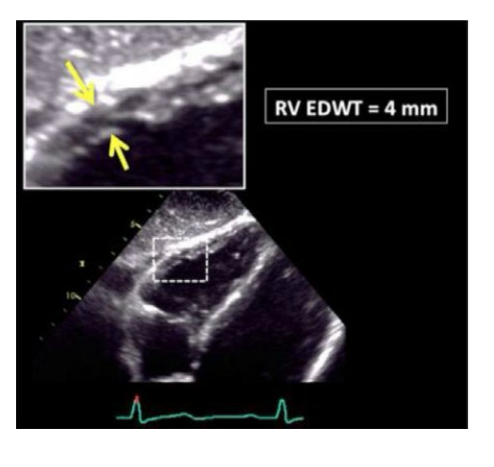

Wall thickness is obtained from what view during which cardiac cycle and what do you want to zoom on?

A thickness of what number is abnormal

what is normal

Wall thickness is obtained from the Subcostal view at end diastole.

Zoom on mid RV wall

A thickness of >5mm is abnormal

<5mmis normal